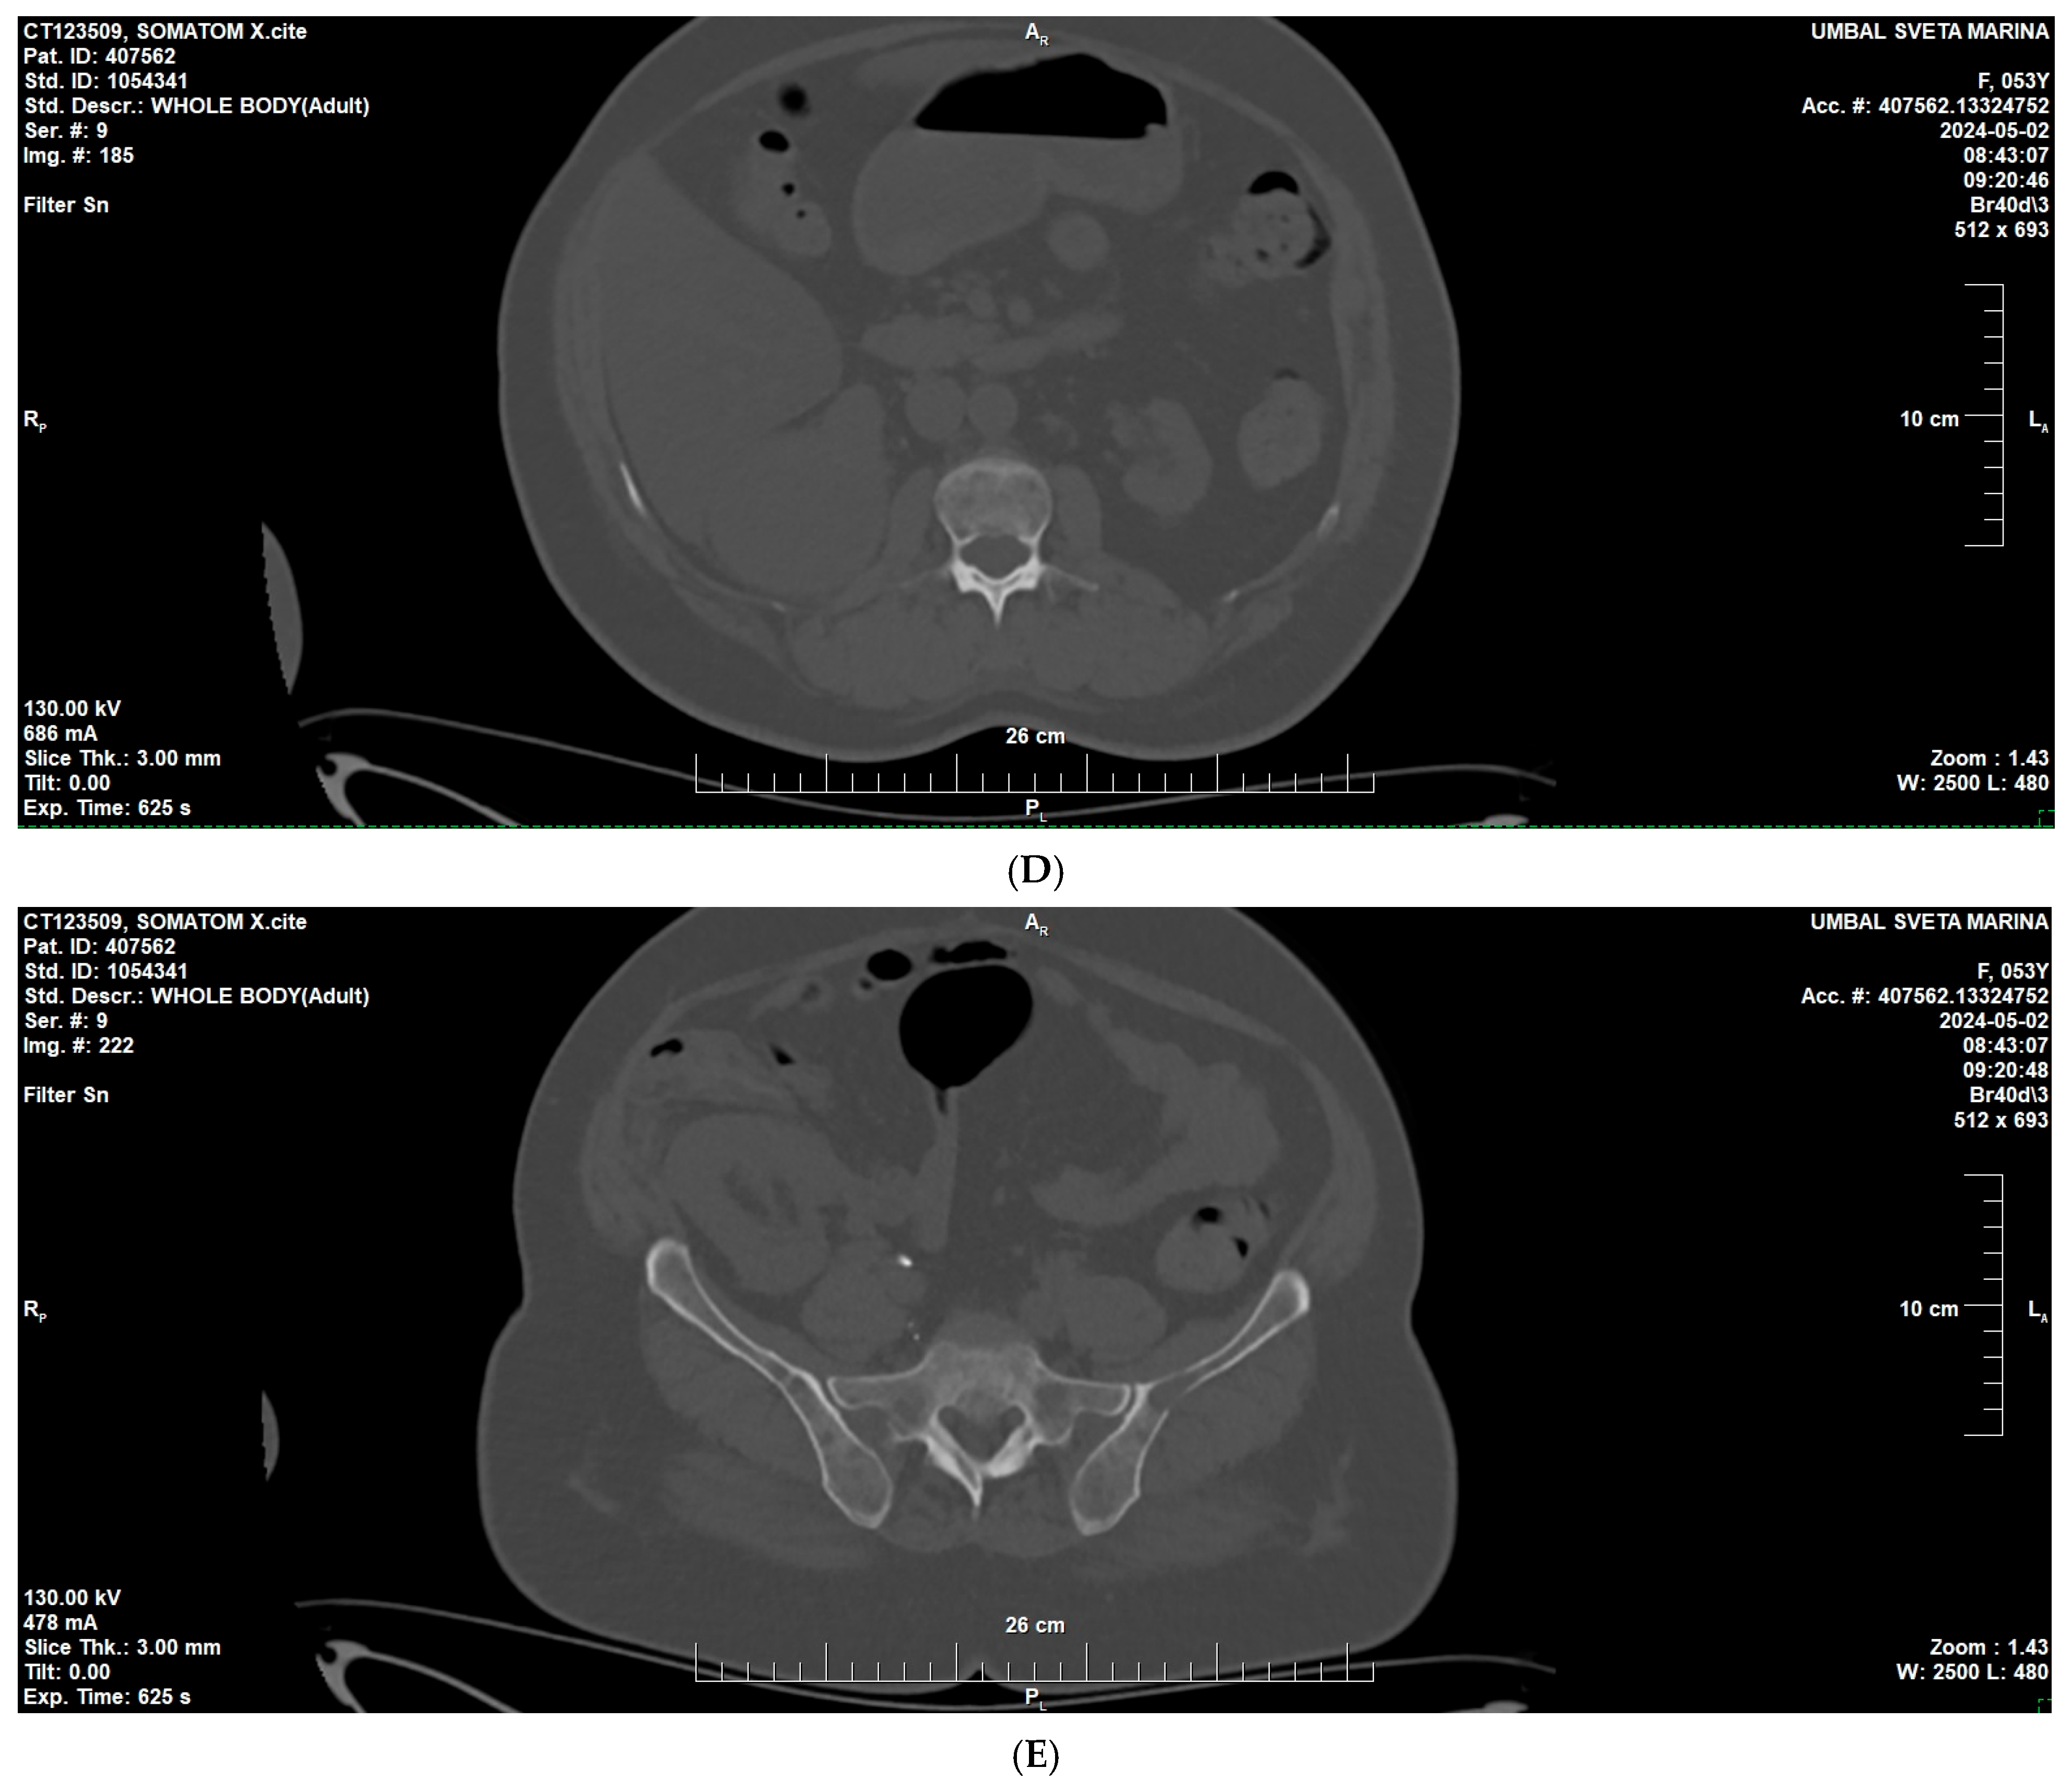

2. Case Presentation